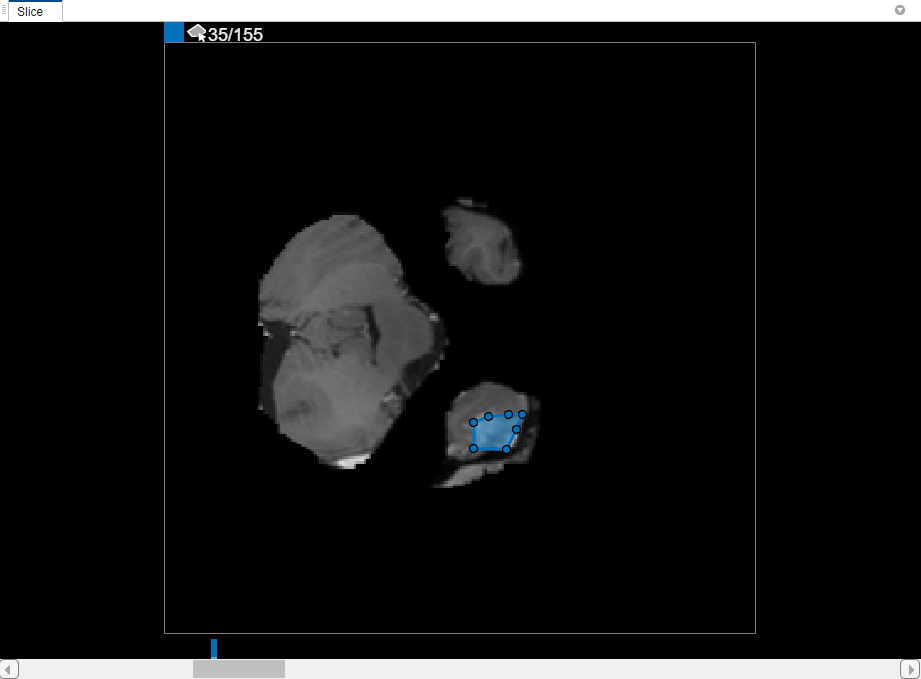

[スライス] ペインで、オブジェクトが最初に現れるスライス (スライス 35) にナビゲートし、その周りに輪郭を描きます。この例の場合、[多角形] 描画ツールを使用します。クリックして頂点を 1 つ作成し、カーソルを動かして再度クリックし、2 番目の頂点を作成して両者を直線で接続します。この手順を継続して接続線を作成します。描画の終了後に頂点を追加するには、ROI のエッジをダブルクリックします。

内挿を使用するには、まず 2 つのスライスに手動で領域を定義しなければなりません。オブジェクトが現れる最初のスライスには既に領域を定義してあります (スライス 35)。同じ手順を使用して、オブジェクトが現れる最後のスライスに領域を定義します (スライス 88)。スライダーの上に、ROI のあるスライスを示す、ラベルと関連付けられた色のバーが 2 つ配置されます。

2 つのスライスにオブジェクトを定義した状態で、[自動内挿] をクリックします。間にあるすべてのスライスに ROI が自動的に定義されます。ROI をもつすべてのスライスが青色のバーで示され、スライス 35 からスライス 88 までが連続したバーのように見えています。